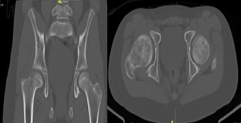

A 12-year-old male patient, who began medical controls in our service in 2018, diagnosed with Legg-Calvé-Perthes disease of the right hip (Figure 1), presenting pain when standing, agitated gait, and claudication. In 2022 in tomographic control (Figure 2) and CT with 3D reconstruction (Figure 3) that evidence right coxa magna and alteration of the femoral sphericity with CAM type morphology, associated with pain and limitation of range of motion, was the reason for which it was decided to perform surgical intervention. Physical exam: Pain and limitation of range of motion (right/left flexion 100°/100°, right/left internal rotation 28°/45°, right/left external rotation 12°/20°, limited abduction due to pain in the right lower extremity).

Figure 3 3D reconstruction Computed Axial Tomography of the right hip.